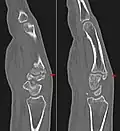

Carpometacarpal bossing (or metacarpal/carpal bossing) is a small, immovable mass of bone on the back of the wrist. The mass occurs in one of the joints between the carpus and metacarpus of the hand, called the carpometacarpal joints, where a small immovable protuberance[1] occurs when this joint becomes swollen or bossed.

The joint between the index metacarpal and the capitate is a fibrous non-mobile joint. Some people have a gene that leads to this growth. It looks like arthritis (bone spurs on each side of the joint) on X-ray. It looks like a ganglion on the hand, but more towards the fingertips.

Carpometacarpal boss is uncommon and there is not much scientific data. Its etiology has yet to be fully defined, but can be congenital in the form of an accessory ossicle (os styloideum) or may be acquired from trauma, repetitive use, or degenerative osteophytosis.[3] The condition usually begins to show in the 3rd or 4th decade.